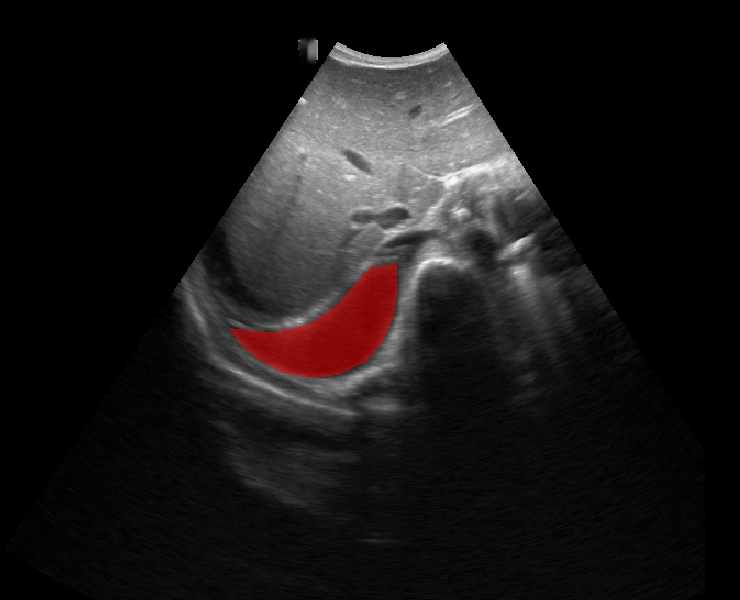

A total of 143 images were acquired from 59 patients. The images were obtained at the left and right PLAPS (PosteroLateral Alveolar and/or Pleural Syndrome) and subcostal views [4] with linear array and curved array (abdominal) ultrasound probes. The data were split according to the use of these probes into two datasets of 51 and 92 images, respectively for linear array and curved array. We denote these datasets as Dataset A (linear array) and Dataset B (curved array). All images were annotated at the time of acquisition to measure the extent of the effusion. These annotations consisted of small crosses at the top and bottom of the deepest area of effusion. See Figure 1 (left column) for example images.

Before being used for training and evaluating the models, each image was automatically cropped using a rectangular/cone mask to remove non-imaging content. Next, we applied an inpainting text algorithm using keras-ocr followed by template matching and edge detection algorithms from opencv to remove the annotations that were added to the images to measure the effusion. Examples of the outputs of this preprocessing are shown in Figure 1 (centre column).

All images in both datasets were manually segmented using the ITK-SNAP software [14] (www.itksnap.org) by a trained observer. Examples of ground truth segmentations are shown in Figure 1 (right column). These segmentations acted as ground truths for training and evaluating the proposed models. Additionally, a second trained observer performed independent segmentations of subsets of 10 random images each from the two datasets. These were used to compute an estimate of inter-observer variability in the manual segmentation process.

Qualitative prediction results of the two proposed models (baseline nnU-Net and nnU-Net with coordinate convolutions) on the two datasets are shown in Figure 2. Tables 1 and 2 summarise the quantitative performances in terms of DSC and area statistics. Histograms of the DSC values are shown in Figure 3. The median DSCs between the manual segmentations on the subsets of 10 images (i.e. the estimates of inter-observer variability) are also shown in Table 1.

Rows 1-2: Dataset A. Rows 3-4: Dataset B.